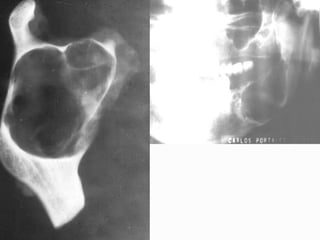

5. Temporomandibular Joint Disorders (3 H)

 Students should display a knowledge and understanding of the:

 The importance of a full and systematic history of present complaint including

previous treatment.

 Method of examination to differentiate between temporomandibular joint

disorders, muscular discomfort and atypical facial pain.

 Special investigations required.

 Value of conservative/surgery/drug therapy for TM joint disorders.

 Conditions that may affect the temporomandibular joint including:

 TMJ dysfunction syndrome



TMJ arthritis and other degenerative disorders

TMJ ankylosis

TMJ dislocation